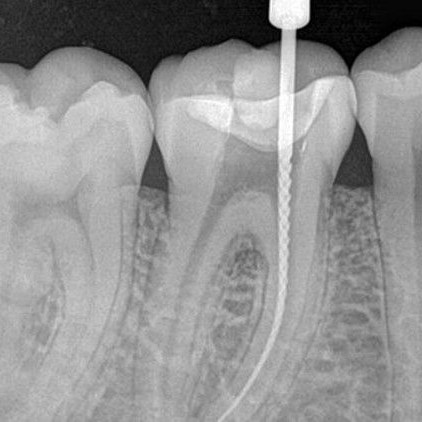

ROOT CANAL